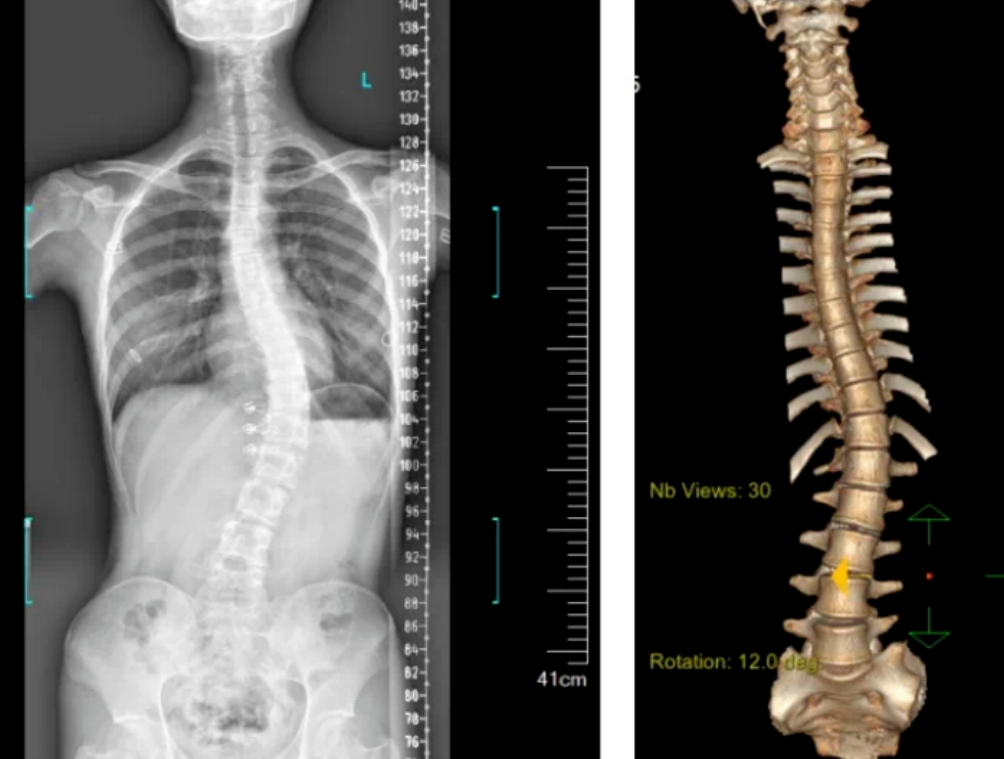

3D機器視覺的脊柱檢測圖

3D視覺技術可以用于自動化的脊柱側彎檢測。通過使用3D成像設備,如結構光或激光掃描儀,機器人可以快速捕捉老年人的脊柱圖像,并利用機器視覺算法分析脊柱的形態和角度,從而判斷是否存在側彎現象。

基于顯揚科技HY-HY-X3 3D機器視覺的脊柱側彎檢測系統,能夠在無需接觸患者的情況下,快速獲取患者脊柱的三維圖像。該系統使用高精度的3D攝像頭,通過結構光或激光掃描技術,捕捉到脊柱的詳細形態。

系統掃描速度為15Hz,精度達到±0.01mm,結合自研智能算法,能夠進行全彩信息學習,還能通過深度攝像頭捕捉人體背部的形態變化,轉化為對應的脊柱形態,并計算脊柱的彎曲角度,從而了解患者的側彎程度。這種方法避免了傳統X光片檢測帶來的輻射風險,實現了無輻射、快速、便捷的篩查。